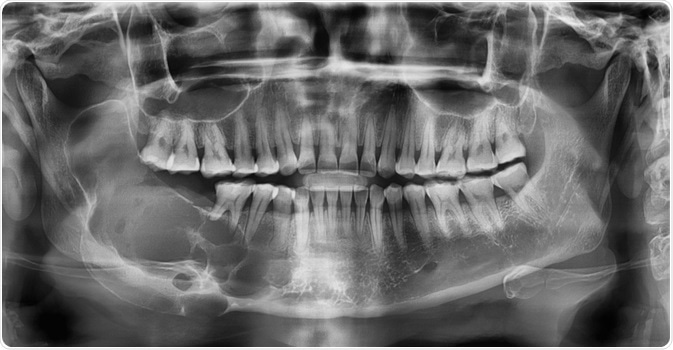

Image Credit: Rames Khusakul/Shutterstock.com

A combination of both clinical examination and an X-ray is commonly used to diagnose suspected ameloblastoma. Referral to an Oral and Maxillofacial Surgeon for a second opinion and confirmation of the diagnosis is fairly usual. Many ameloblastomas are discovered by chance at the dentist during ordinary dental operations or X-rays.

When a tumor seems to be an infection, causing discomfort and swelling in the jaw, it is usually treated with antibiotics. When antibiotics fail to ease the symptoms, a regular X-ray is taken to further check the symptoms, and the probable ameloblastoma is discovered. Further tests including CT scans, MRI scans, and a biopsy of the bone are used to confirm the presence of the tumor.